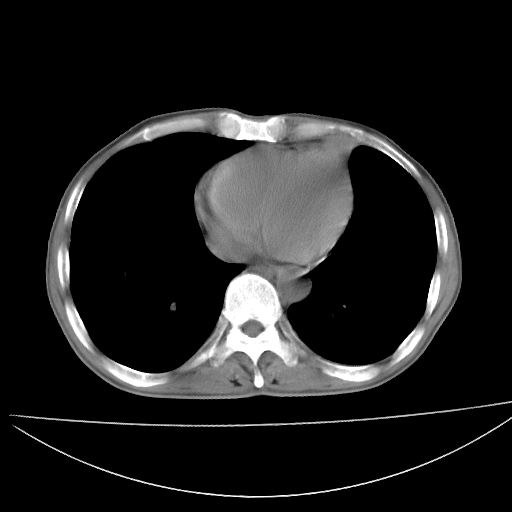

以下是引用杀毒软件在2009-4-28 17:58:00的发言:[br]考虑----左肺慢性肺脓肿形成继发上叶含气不良---抗炎后复查---待排肿瘤所致[br][br][本贴已被 杀毒软件 于 2009-4-28 18:01:26 修改过]